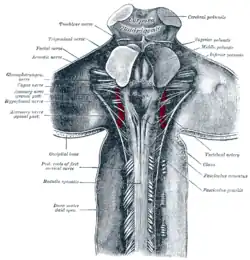

Parte superior da medula espinal e partes posteriores e mediais do encéfalo; aspecto posterior, expostos in situ.

Parte superior da medula espinal e partes posteriores e mediais do encéfalo; aspecto posterior, expostos in situ. -